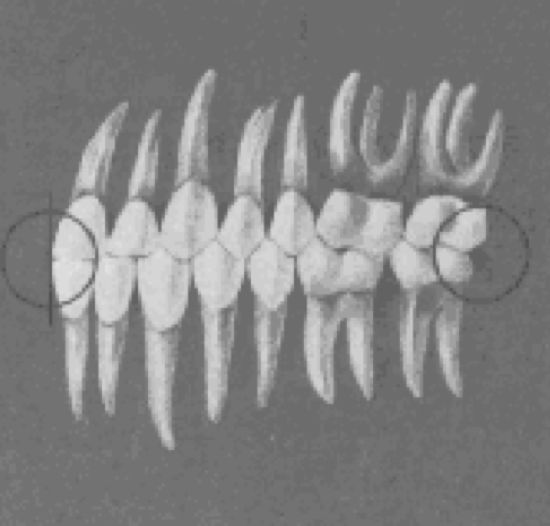

Rotations

teeth should be free of undesirable rotations

Tight contacts

contact points should be tight (no spaces)

Occlusal plane

Planes of occlusion

flat to slight curves of spee

Intercuspation of teeth

best when the plane of occlusion is relatively flat

Deep curve of spee

more contained area for the upper teeth, making normal occlusion impossible

reverse curve of Spee

extreme form of overtreatment, allowing excessive space for each tooth to be intercuspally placed